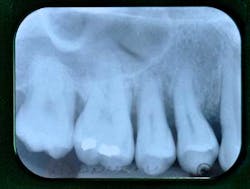

Fig. 1: Radiographic status of a 30-year-old Caucasian female

The clinical examination shows:

- Periodontal examination: The patient has very good oral hygiene, 6 mm to 9 mm pockets, bleeding on probing, and tooth mobility (especially tooth No. 4).

- Dental examination: Tooth No. 14 has been endodontically treated and now holds a PFM crown. Tooth No. 3 holds two tiny alloys.

- Functional examination: The patient reports no musculo-articular symptoms though lateral jaw movements exhibit working-side interferences on the premolars.